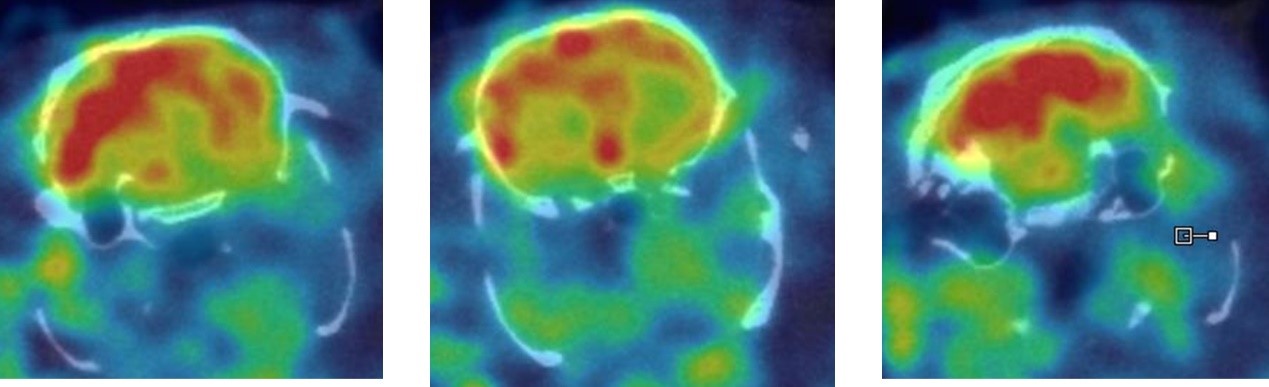

1、神經(jīng)系統(tǒng)SPECT成像

大鼠腦部SPECT成像:99mTc-HMPAO:腦血流灌注顯像劑,用于腦血管疾病,腦外傷,癲癇,癡呆癥,腦死亡的診斷;用于精神疾病的腦功能及正常腦生理功能活動(dòng)的研究。進(jìn)入腦組織的99mTc-HMPAO構(gòu)型改變而轉(zhuǎn)變成水溶性化合物,無(wú)法再次通過(guò)血腦屏障而滯留在細(xì)胞內(nèi),因此能在腦內(nèi)長(zhǎng)時(shí)間滯留。120 MBq,30 min uptake,30 min SPECT。

神經(jīng)系統(tǒng)成像.jpg